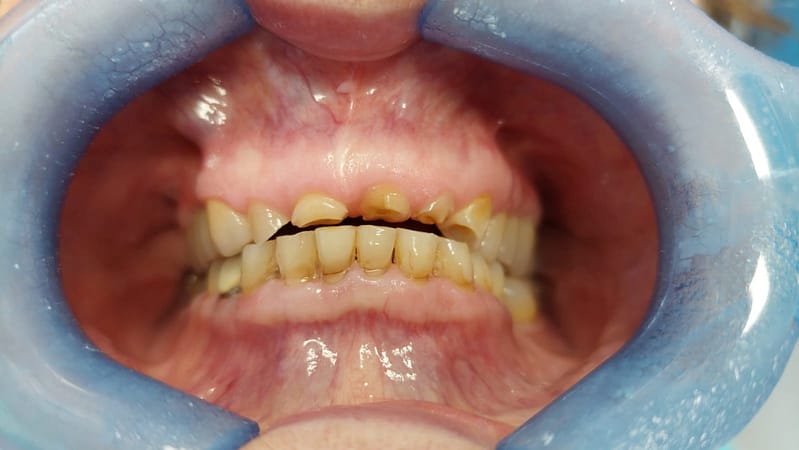

Usura dentale

CHE COS’È? L’usura dentale è un fenomeno in forte crescita negli ultimi anni, ed è […]